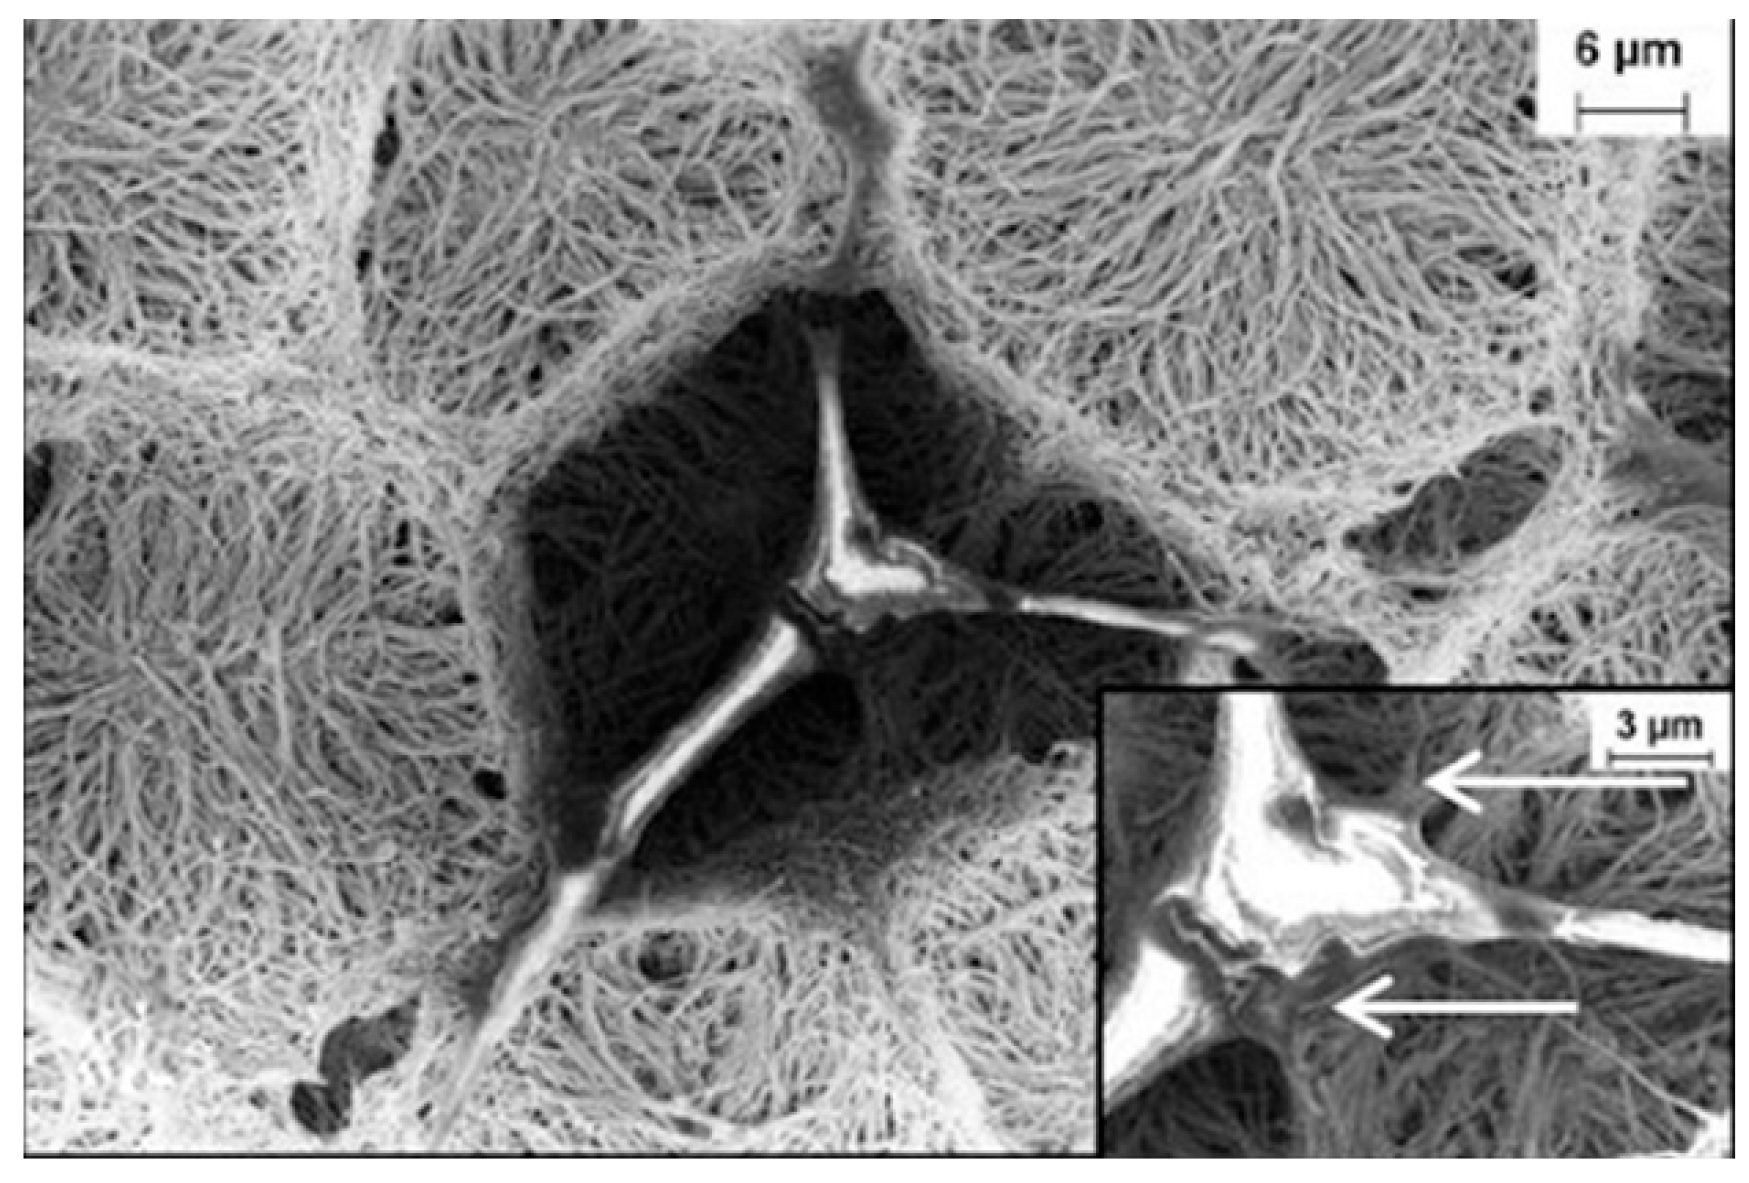

3.1. Carbon Nanotubes

- Sirivisoot, S.; Yao, C.; Xiao, X.; Sheldon, B.W.; Webster, T.J. Greater osteoblast functions on multiwalled carbon nanotubes grown from anodized nanotubular titanium for orthopedic applications. Nanotechnology 2007, 18, 365102. [Google Scholar] [CrossRef]

- Correa-Duarte, M.A.; Wagner, N.; Rojas Chapana, J.; Morsczeck, C.; Thie, M.; Giersig, M. Fabrication and Biocompatibility of Carbon Nanotube-Based 3D Networks as Scaffolds for Cell Seeding and Growth. Nano Lett. 2004, 4, 2233–2236. [Google Scholar] [CrossRef]

- Abarrategi, A.; Gutierrez, M.C.; Moreno Vicente, C.; Hortiguela, M.J.; Ramos, V.; Lopez Lacomba, J.L.; Ferrer, M.L.; Del Monte, F. Multiwall carbon nanotube scaffolds for tissue engineering purposes. Biomaterials 2008, 29, 94–102. [Google Scholar] [CrossRef]